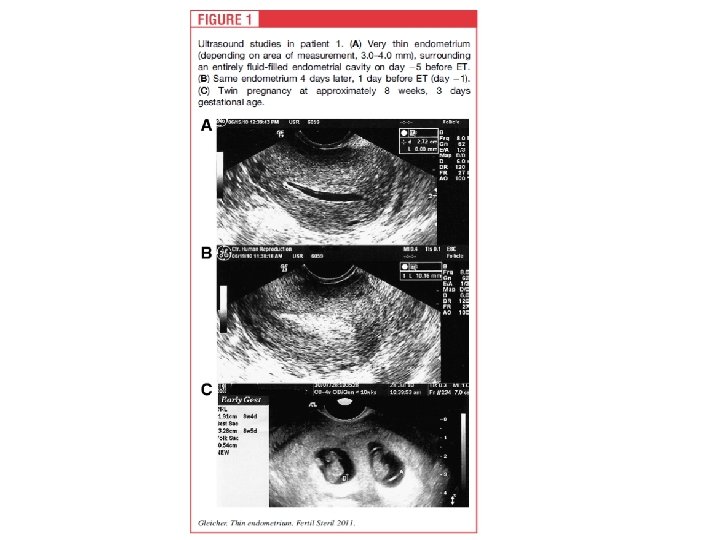

Patient P. , 38 y. old, with tubal factor of infertility, had three tubal and ovarian surgery episodes and six IVF attempts in anamnesis. Previous IVF attempts had complications as poor response, thin endometrium and unexplained fluid accumulation in uterine cavity during ovarian stimulation. Two IVF attempts ended first trimester miscarriages with abnormal fetus karyotype. Ovarian reserve was low (serum AMH level <0. 5 ng/ml). The seventh IVF attempt was performed according to modified natural protocol. The antagonist daily injection with concomitant low FSH dose was administrated when leading follicle reached more than 15 mm in diameter. Three days later, when the follicle was 19 mm, ovulatory dose of 5000 IU HCG was administrated and 35 hours later follicle punction was performed. One mature COC was received. 24 hours after follicle punction, uterine cavity was flushed by 30 IU of recombinant G-CSF (Grasalva, Fillgrastim, TEVA, Israel) in one ml solution. 72 hours after follicle punction one 8 -cell embryo was transferred. Three weeks after ET monochorionic diamniotic twin was detected by ultrasound examination. Screening US scan on 12. 5 weeks of pregnancy showed absence of any chromosomal abnormality sings. Now, monozygotic female twin pregnancy reaches 20 weeks without any complications.

Significance of CSFs in human reproduction CSF-1 (M-CSF) CSF-2 (GM-CSF) CSF-3 (G-CSF) Ovary Regulates steroidogenesis, enhances gonadotropin action on granulosa cells (1, 2) Enhances follicular development (7), histamine release during ovulation (6) Maintains number of primordial follicles(14), produced by granulosa cells in mature and ovulated follicles (15 -16) Endometrium M-CSF is produced by uterine glandular epithelial cells, involved in endometriosis pathogenesis (3) GM-CSF and GM-CSF-R are expressed with peak at midsecretory endometrium (8) G-CSF produces by luteal phase endometrium (17) Pregnancy and Placenta Plays a role in placental development (4) Growth factor for trophoblast and other placental cells (9), produced by trophoblast and u. NK cells (10), involved in pathogenesis of preeclampsia (11) Produces by trophoblast cells (17), affects decidual macrophages (18) Clinical use M-CSF can enhance oocytes number and PR in poor responders (5) Treatment of repeated implantation failure (12), GM-CSF production in endometrial co-culture associated with outcome (13), addition to culture (Embyo. Gene) FF level may be a predictor of PR in n. IVF cycles (19), S level may be a pedictor of pregnancy (20), treatment of thin endometrium (21), and RMs (22)